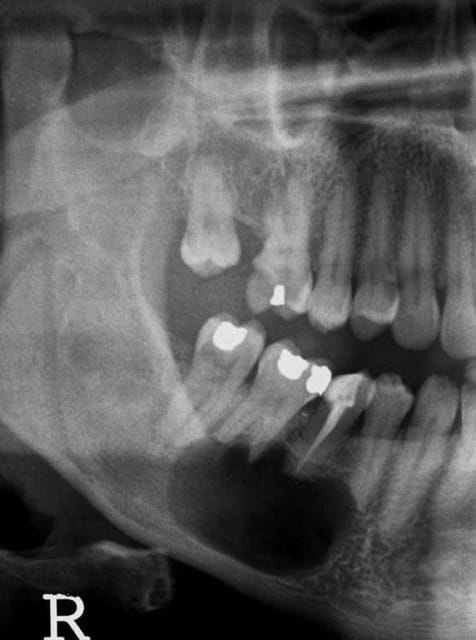

Voilà une pano réalisée suite à un rv

de contrôle . Le patient venais pour du tarte..

c'est quoi ton diagnostic sur ce cas et le traitement à suivre , Antoine ?

peut-être un ameloblastome, difficile à dire il manque trop d'informations

si c'est le cas, traitement par enucléation en chirurgie

Est-ce que la 46 est vitale ?? Peut-être s'agit-il d'un kyste osseux solitaire ??

Il y a pas de bordure de condensation osseuse et l'image est assez caractéristique on dirait que la masse radioclaire contourne les apex des dents. De plus, le patient a déjà eu des kystes traités avec conservation des dents. Et le kyste osseux solitaire se traite pas simple trépanation pour remplir la cavité de sang car souvent vide ou avec un peu de sérum.

Sinon c'est peut-être simplement une kyste radiculodentaire en rapport avec la 45.

Condensation osseuse autour apex dent dépulpée mais aussi peut être image apicale sur racine distale de 6 (?), pourquoi pas essayer de reprendre endo de prémo et voir ce qu'il se passe? Si tu as liquide qui remonte par racine catheterisée c'est à mon avis elle la cause ou en tout cas ça vaut le coup d'essayer de la retraiter (CaOH2 et voir...)et de traiter la lésion par cet accés. Virer le kyste par chir et maintenir les autres dents vitales (si elles le sont bien...) ma parait délicat...